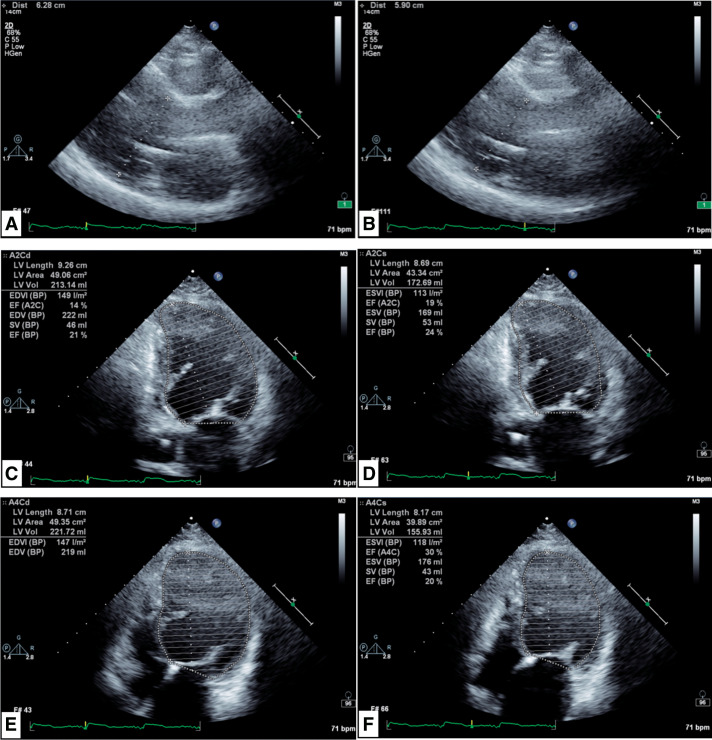

Case presentation: A 64-year-old female with a history of DC and sustained ventricular tachycardia, who had received cardiac resynchronization therapy with defibrillator implantation, underwent breast cancer surgery. She had been repeatedly hospitalized for heart failure with an LVEF of 19% and New York Heart Association (NYHA) Class III status, and heart transplant surgery was considered. However, a screening computed tomography scan revealed right breast cancer, and neither heart transplantation nor breast cancer surgery was performed. Endocrine therapy was initiated and failed 48 months after administration. Although the LVEF remained low at 21%, the NYHA classification improved to Class II, and she had not been hospitalized for heart failure for an extended period since her breast cancer diagnosis. Therefore, breast cancer surgery was performed under general anesthesia and no postoperative complications were observed throughout the course of the surgery.